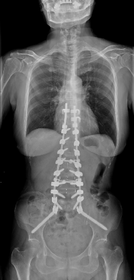

思春期特発性側弯症が高度に進行した症例です。最大側弯角度は113°であり、100°を超える側弯の手術は一般的に神経合併症が危惧されます。神経合併症を極力防ぐため、また侵襲を低減する目的で、同じ入院期間に2回に分けて段階的に矯正手術を行いました。1回目に最も側弯の強い箇所に対して側方から椎体間解離を行い、2回目に後方から全体のバランスが良くなるように慎重に矯正固定術を施行しています。

神経合併症はなく、術後の最大側弯角度は15°に改善(矯正率:87%)、背中の大きなコブも無くなっているのが分かります(赤矢印)。神経合併症が発生しないように慎重に手術を行うのは当然ですが、側弯を治すだけでなく横から見た姿勢を治すことにも留意しています。